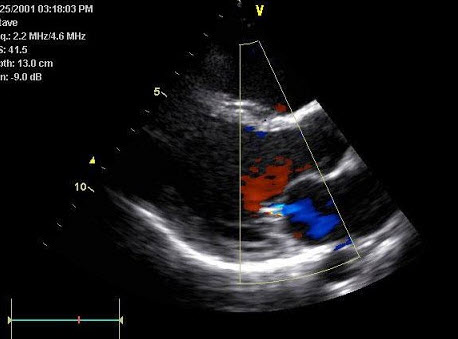

54、单项选择题

某患者左室长轴切面超声心动图如图所示,诊断为()

A.正常声像图

B.主动脉瓣关闭不全

C.二尖瓣关闭不全

D.室间隔缺损

E.房间隔缺损

55、单项选择题 胎盘早剥的临床和超声表现,下列哪一项是错误的()

A.妊娠晚期阴道出血